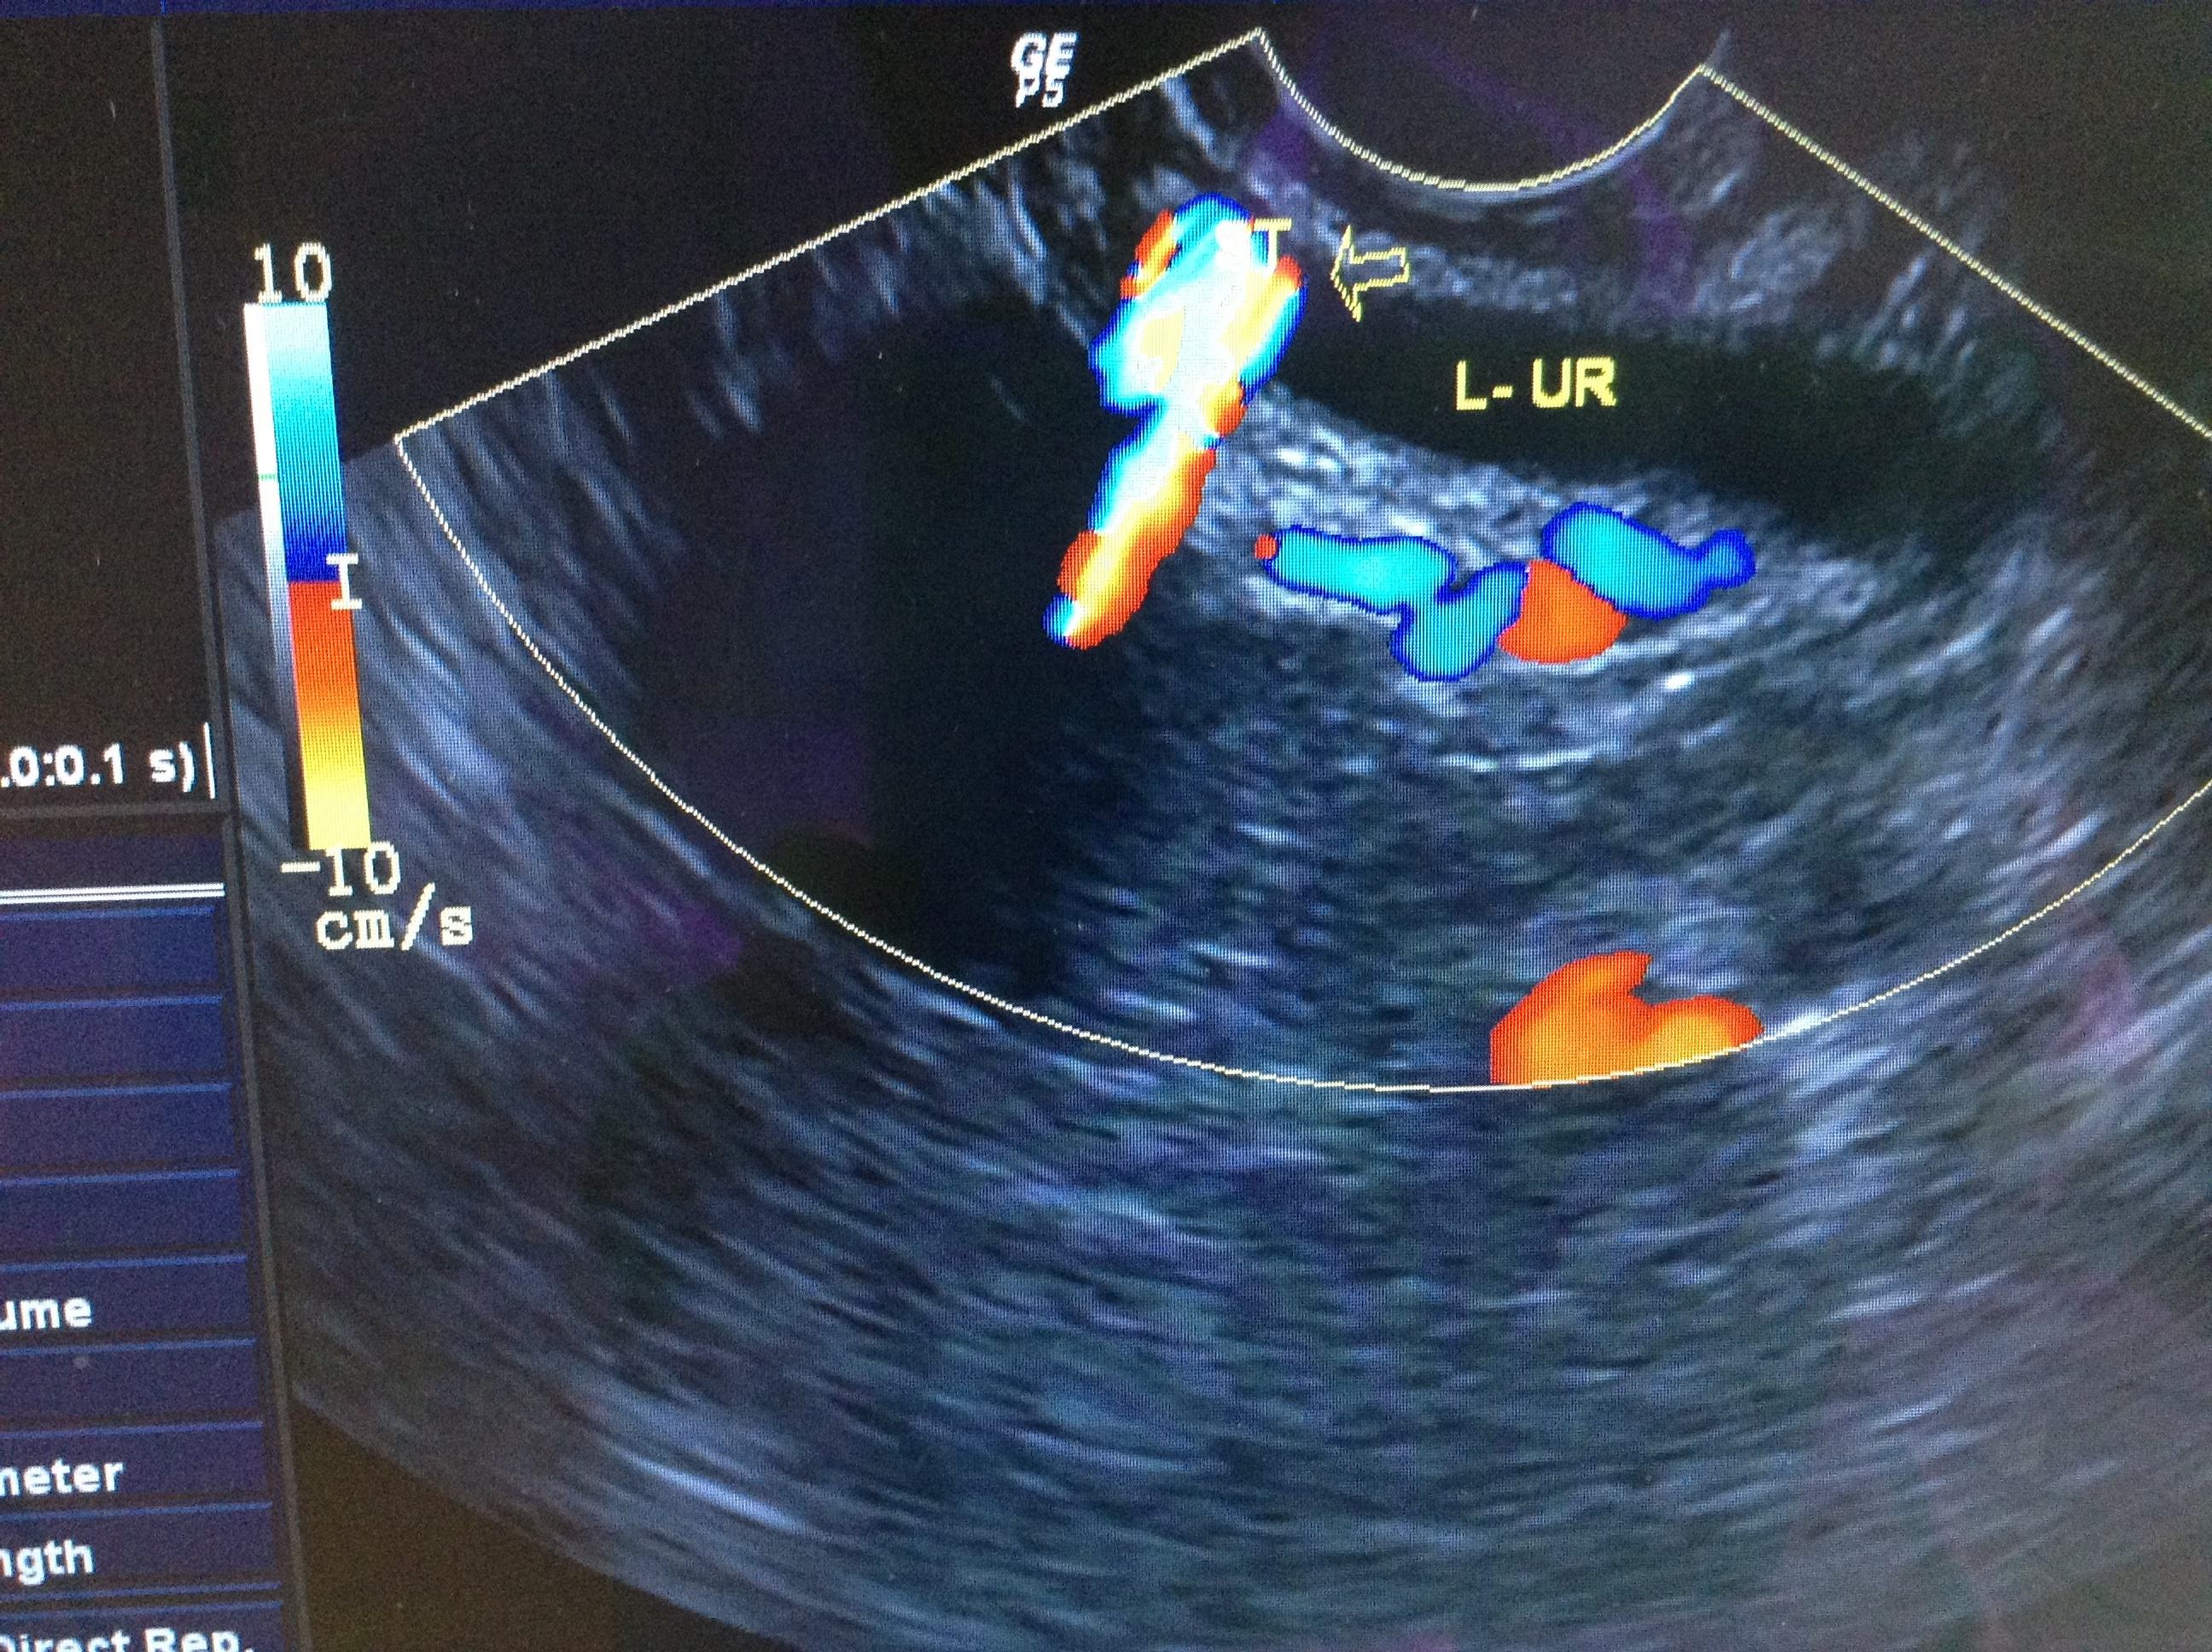

那么,第一次做阴超到底是种什么体验呢?其实并没有想象中那么疼,阴超所用的仪器是阴道探头,粗细程度和人的大拇指差不多。在做阴超的时候,医生要在探头上涂上消毒耦合剂,并在上面罩上一个套子,在套子上也涂上足量的耦合剂。这既能防止探头对女性阴道的伤害,也能够增大耦合剂的面积,更加全面的探查里面的情况。

做好准备之后,医生会将探头缓慢地放进去,让被检查者慢慢的适应,同时观察仪器上的图像,调整探头的位置,以便更加清晰明了的观察里面的全部情况。这时被检查者不要有过度的紧张或者羞怯的情绪,这样很可能会影响检查的结果,导致结果不准确,会在一定程度上干扰医生的判断。

另外阴超还有一个优点:阴超观察的情况,比起B超来讲更加直观。它不仅能观察到孩子的生长发育情况,还能够清楚的看到子宫和卵巢的情况,甚至连卵泡都可以明显的观察出来,这是阴超优于B超的最大优点,也是阴超独有的特征。

做阴超不仅不会使妈妈们产生疼痛,对宝宝也没有什么不好的影响。在做阴超时,探头只在阴道内部活动,不会深入到子宫的位置,所以不会对胎儿产生影响,反而能更好的观察到孩子的情况,及时发现宫外孕等症状,在临床上有很重要的意义。